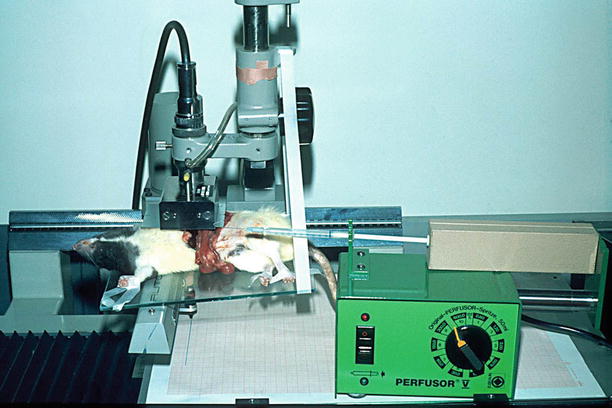

Under general anesthesia, the rat, with an optimal weight of about 250 g, is fixed lying on the back. The abdomen is opened via an incision beneath the left costal margin or a midline incision. The intestine together with the spleen is rotated to the right side and fixed with broad hooks (Fig. 2.1). With the help of two Q-tips, which are rotated in contrary direction, the aorta is exposed.

Fig. 2.1

Rat weighting around 250 g, the intestine together with the spleen is rotated to the right side and fixed with broad hooks; the left side of aorta is exposed

The patency of the lymphatic grafts and the function as well were examined by injection of 131 I gamma globulin. The injection was performed within the cisterna chyli using an infusion pump. The activity was measured in the area above the thoracic duct in the chest (Fig. 2.12).

Fig. 2.12

Assessment of function after reconstruction of the abdominal thoracic duct by lymphatic grafts, injection of 131 I gamma globulin in the cisterna chyli, measurement above the thorax